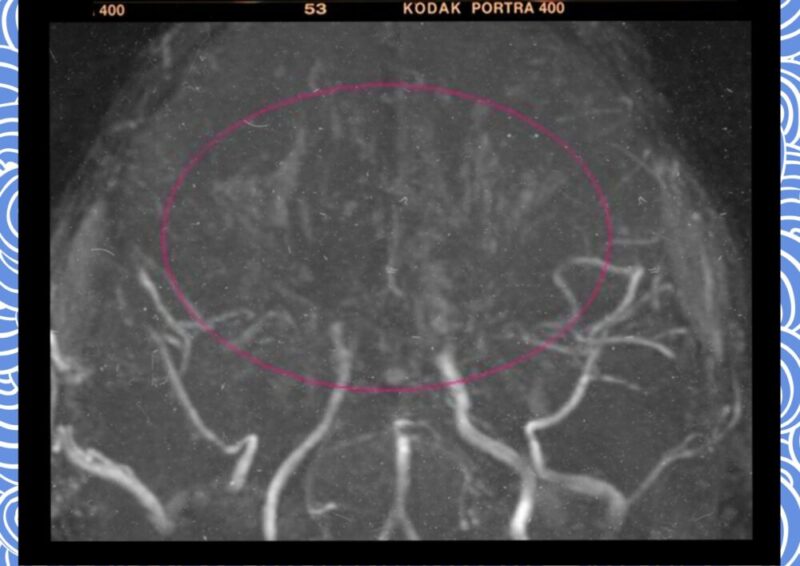

이러한 일상적인 행동이 갑작스러운 사지 마비나 힘 빠짐 증상을 유발하는 배경에는 인체 뇌혈관 설계의 독특한 보상 기전과 생리학적 반응이 복합적으로 얽혀 있다. 뇌로 가는 주 혈관인 내경동맥 끝부분이 좁아지면서 뇌는 부족한 혈류를 공급받기 위해 미세 혈관들을 비정상적으로 생성하게 되는데, 이것이 마치 담배 연기가 모락모락 피어오르는 모양과 비슷하다고 하여 일본어로 ‘모야모야’라는 이름이 붙었다.

인체의 뇌혈관은 원래 대뇌 동맥륜(Circle of Willis)이라는 구조를 통해 어느 한쪽 혈관이 막히더라도 다른 쪽에서 피를 돌려받을 수 있도록 설계되어 있다. 그러나 모야모야병은 이 설계 자체가 무색해질 정도로 내경동맥 말단 부위가 양측성으로 좁아진다. 뇌는 생존을 위해 급하게 뇌 기저부에 그물망 같은 미세 혈관들을 만들어내지만, 이 혈관들은 매우 얇고 약해서 효율적인 혈류 공급이 어렵다. 또한 혈압 변화에 취약하여 쉽게 터질 수도 있다. 소아의 경우 뇌출혈보다는 주로 뇌경색이나 허혈 증상으로 나타나며, 성인이 되어서 발견되는 경우에는 뇌출혈의 빈도가 높아지는 특징을 보인다.